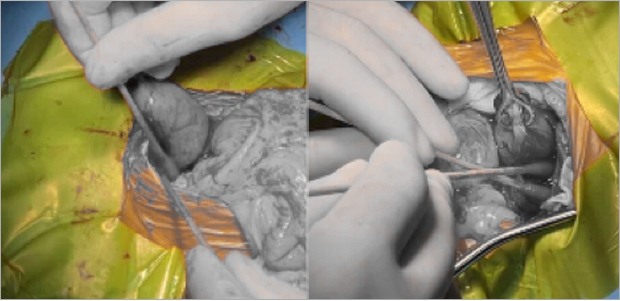

복강경 간생검

강아지 간생검 검사는 간질환의 원인을 알 수 있는 가장 정확한 검사입니다.

복강경 장비를 사용해 1cm이하의 절개창을 내어 간조직을 확보하고 조직검사를 진행할 수 있습니다.

출혈여부 직접 볼 수 있어 안전하고, 평가에 필요한 적절한 크기의 샘플을 얻을 수 있어 진단적 가치가 높은 방법이며,

수술적 개복을 통한 생검 방식에 비해 매우 작은 절개부 (1cm이하의 절개부 2부위)를 가지는 간생검 방식입니다.

케이스1

케이스2

- 수술 직후

- 수술 5일차

- 수술 3주차